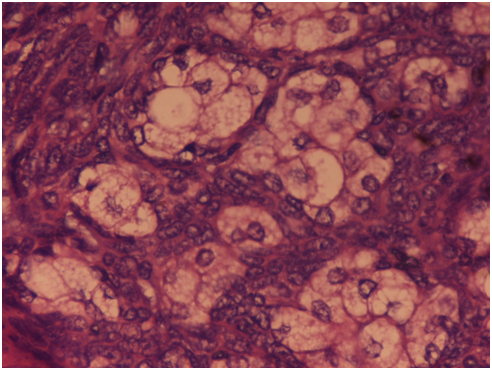

A 42year male presented to the skin outpatient department with chief complains of a single brownish painless lesion on his right cheek for the past one year. On examination, it was ulcerated and nodular, measuring 1.5×1.5cm in size. A clinical diagnosis of pigmented basal cell carcinoma (BCC) was made. The nodule was completely excised and the specimen was sent for histopathological diagnosis. On microscopic examination, section showed lobules and nests of tumor cells embedded in the dermis. Tumor cells were uniform with hyperchromatic nuclei and scant cytoplasm. Tumour islands also showed areas of retraction artifact as well as peripheral palisading of the nuclei on the periphery of the nests (Figure 1). However few aggregates of basaloid cells showed clusters of a sebaceous duct-like structure, containing keratinous debris. These clusters were mainly comprised of squamous cells with the peripheral part containing basaloid cells. Clusters also contained scattered vacuolated cells, with foamy cytoplasm (Figure 2). So a final diagnosis of Basal cell carcinoma (BCC) with sebaceous differentiation was given. The patient was completely asymptomatic after 1year of follow up period.

Figure 1 Section shows lobules and nests of tumor cells embedded in the dermis, with uniform hyperchromatic nuclei and scant cytoplasm. Tumour islands also showed areas of retraction artifact as well as peripheral palisading of the nuclei on the periphery of the nests. Hematoxylin and Eosinx10X.